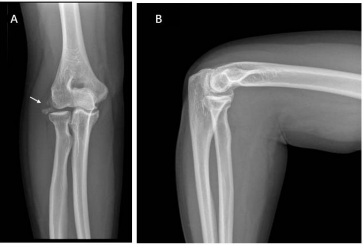

A 44year-old woman presented with limitation of right elbow motion and progressively worsening with pain associated elbow movements. The pain was present when the patient was at rest, and aggravated when the elbow in motions. She did not describe any swelling but with catching, locking symptoms. The pain was started six-years ago after fell over accidently on an outstretched hand. After the accident she visited at emergency department and radiological imaging did not revealed any abnormalities in her elbow. For pain and swelling, elevation and cold-pad applied and then she was discharged home with pain medications. Her pain was relieved a few weeks post injury, however two years ago she was presenting in outpatient clinic, complained right elbow pain associated with weight lifting and pushing up from chairs. Initially her pain was managed as lateral epicondylitis but not effective. On clinical examination, varus stress, elbow Pivert shift tests were positive indicating lateral ulnar collateral ligament (LUCL) laxity (probably from old injury). Radiographs showed a few bony ossicles over lateral epicondyle and lateral radio-capitalum joint, however no bony abnormalities in anterior and posterior elbow joint space (Fig 1). CT scans showed that calcified fragments over lateral elbow joint and a tiny calcification lesion at the olecranon fossa (Figure 2 and 3).

Figure 1: Six years ago, the patient had right elbow injuries, but presented in clinic complained with lateral elbow pain which was managed as lateral epicondylitis. After a few weeks’ physiotherapy & physical therapies her pain was not relieving, Radiographs showed a few bony ossicles over lateral epicondyle and lateral radiocapitalum joint (A), however no bony abnormalities in anterior and posterior elbow (B).